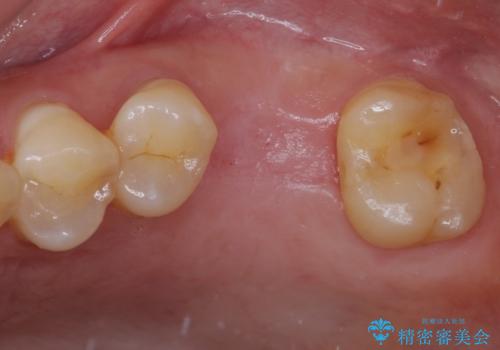

割れてしまった奥歯 サイナスリフトによるインプラント補綴治療

- 近医にて歯が割れている可能性があると言われて来院された患者様です。

歯が割れているかどうかは、顕微鏡下で破折を確認することになりますが、割れていなかった場合には根管治療を行った上で補綴治療を行うことになるため、破折が確認できるまでは根管治療を行う前提で治療を進めて行くこととしました。

破折した場合にはインプラントを埋入した上で補綴治療を行うこととしました。

初診時の診察所見では、破折の可能性は低く、根管治療を前提とした治療にて説明をしておりました。

詰められた材料や壊死した組織を除去したところ、鮮明な破折線が認められたため、速やかに抜歯し、傷や骨の治癒を待って、サイナスリフトにより骨高さの低い部分にインプラント埋入を行いました。